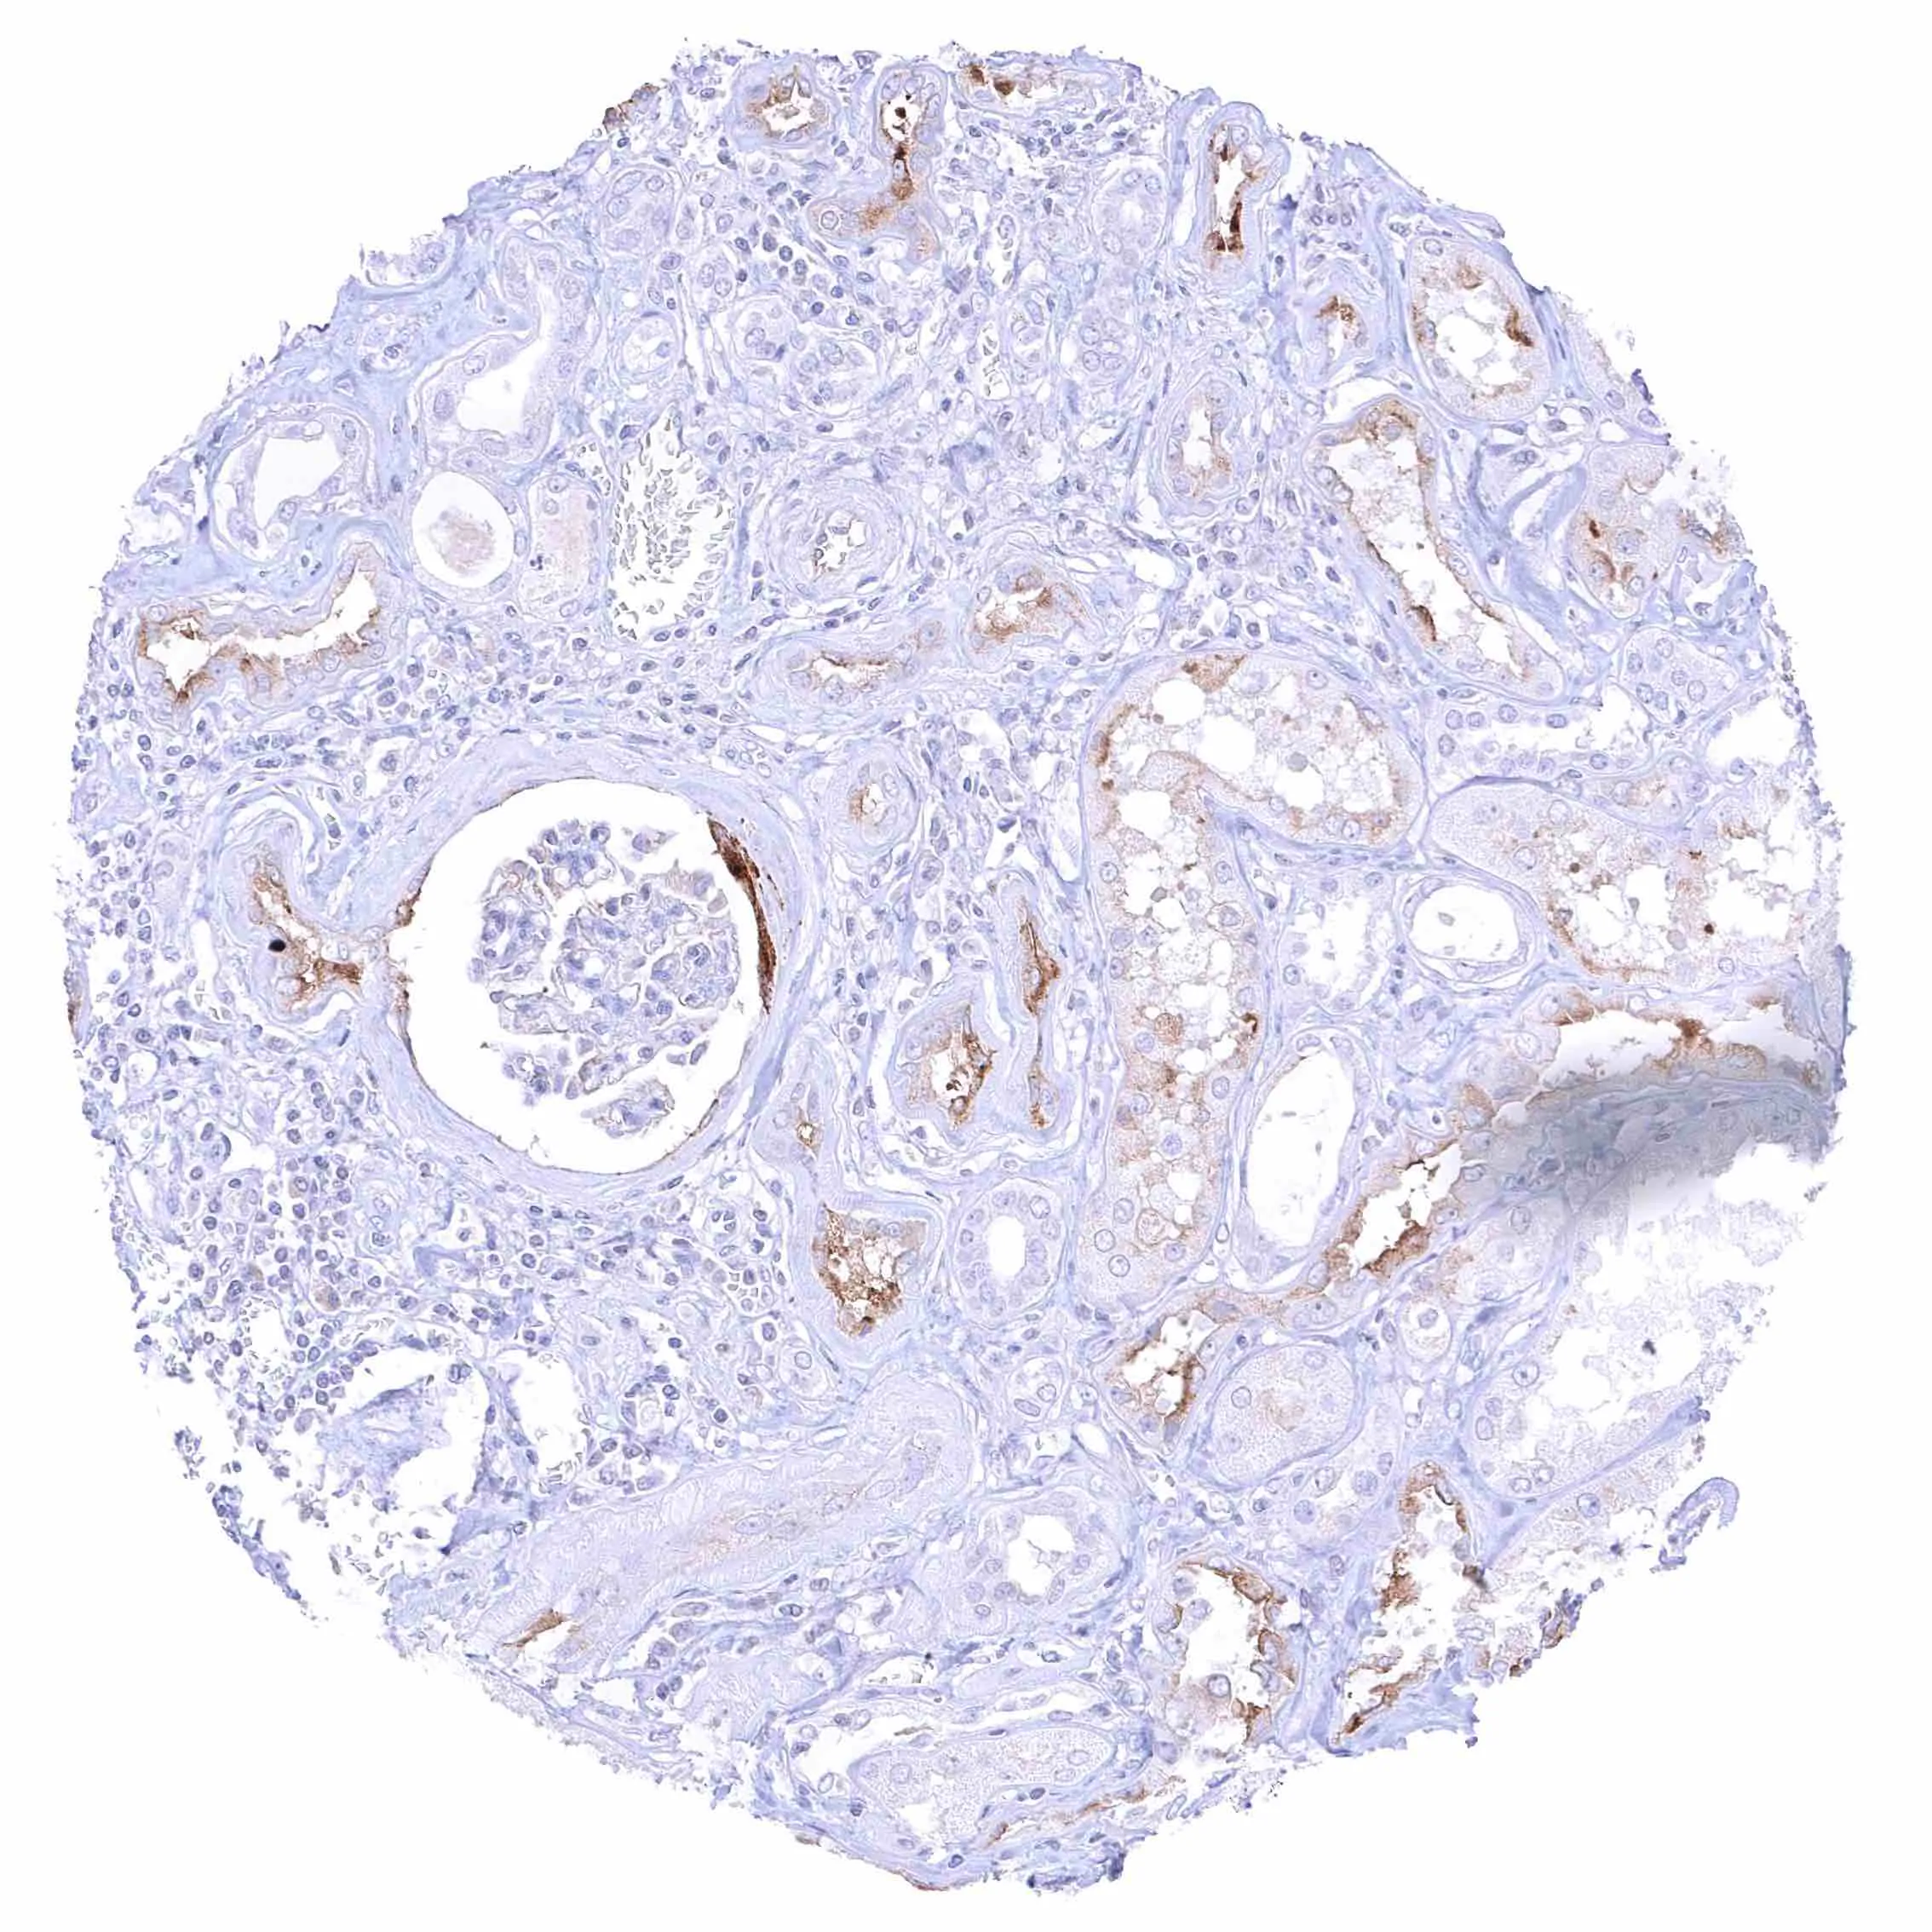

Seminal vesicle – Intense membranous NPR-C staining at the luminal cell border of endothelial cells of small blood vessels.